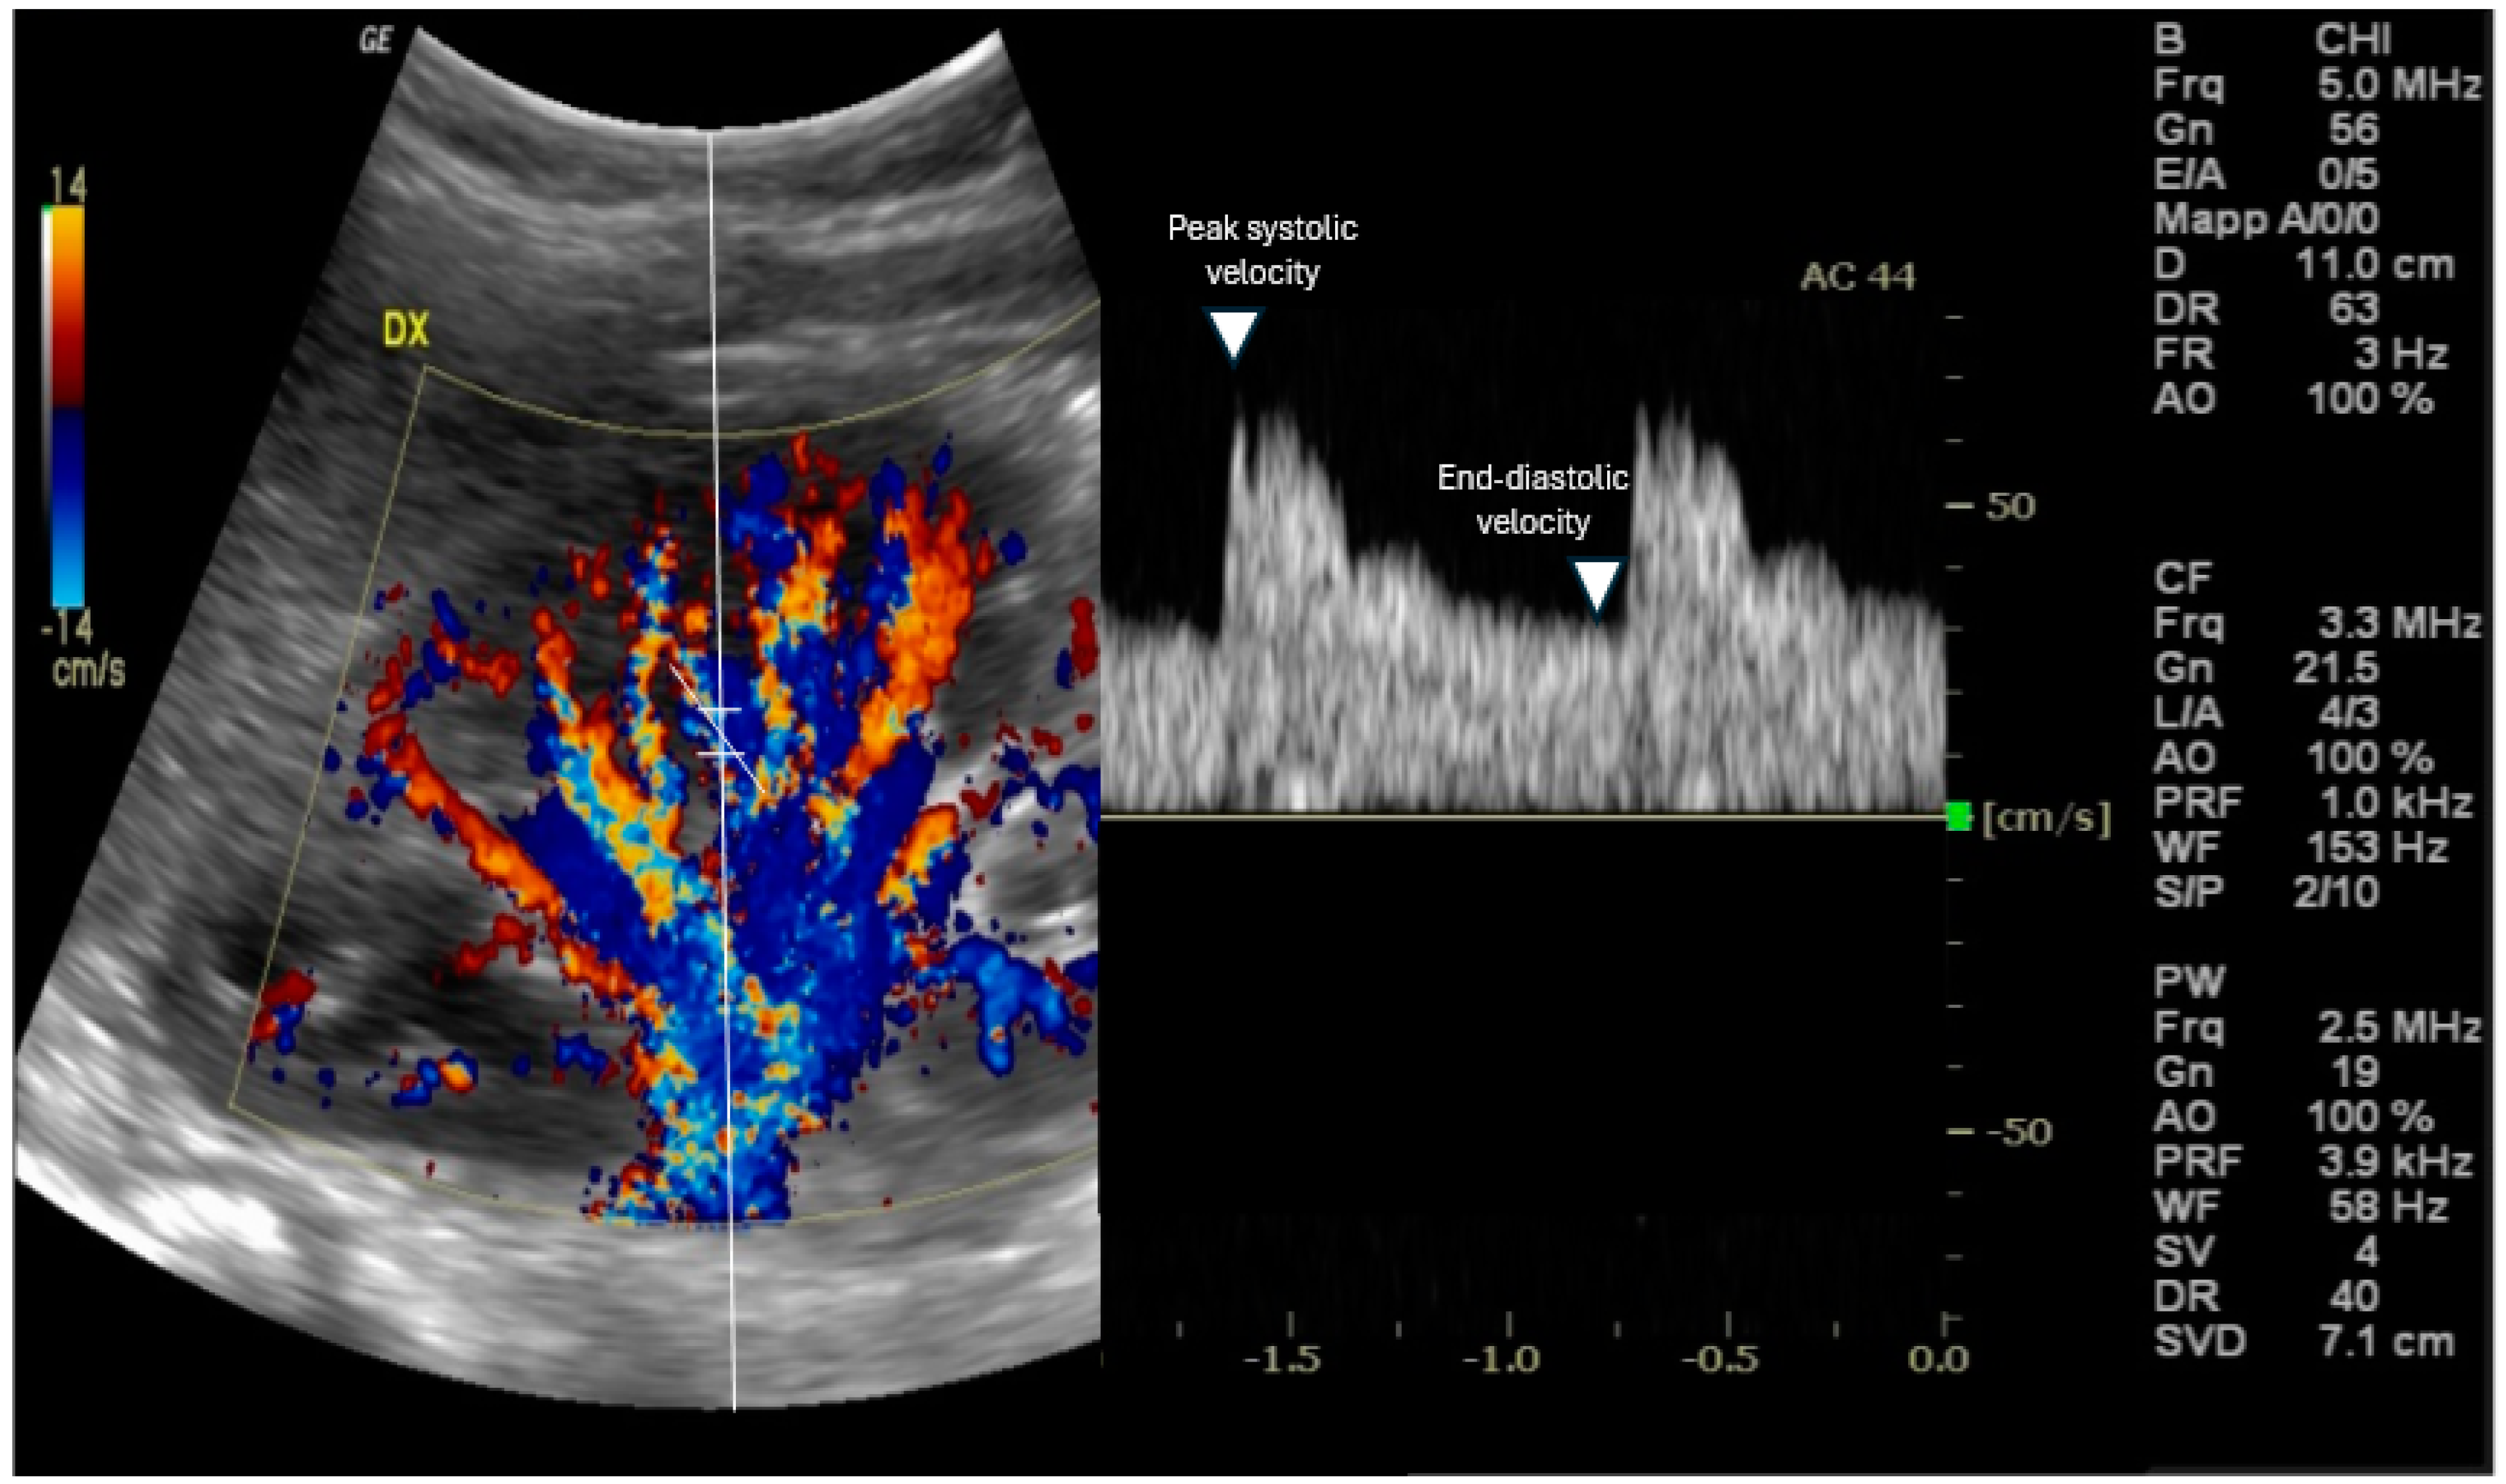

Doppler ultrasonography is a non-invasive imaging technique that enables real-time visualization of blood flow in renal vessels [9]; RRI is assessed using Doppler ultrasonography. The procedure usually occurs with the patient typically either in the supine position or in a slight lateral decubitus position to provide optimal exposure of the kidneys [10]. The kidney is identified, and its anatomy is evaluated via B-mode ultrasound, then, color Doppler augmentation allows for the detection of the main renal artery and its branches inside the kidney [11] [Figure 1].

Figure 1.

Evaluation of the renal resistive index using Doppler ultrasound. The transducer is placed in an interlobar artery, and the spectral Doppler examines the peak systolic and end-diastolic velocities.

This usually includes three types of Doppler to obtain flow information, to visualize subtle and slow blood flow, and to show blood flow velocity over time as a waveform. Usually, a lower frequency, the curvilinear transducer, is preferred (typically 3.5 to 5 MHz) in adult patients since both renal arteries and kidneys are in a deep location. A pulsed wave Doppler sample volume is located in an interlobar or arcuate artery at the corticomedullary junction in most cases [12] in addition to the peak systolic velocity [PSV] and end-diastolic velocity [EDV] measurements from the arterial waveform. Therefore, RRI is calculated using the formula: RRI = (peak systolic velocity − end-diastolic velocity)/peak systolic velocity [2]. At least three measurements should be taken from separate interlobar arteries in each kidney, and the mean value is considered for the final RRI [6].